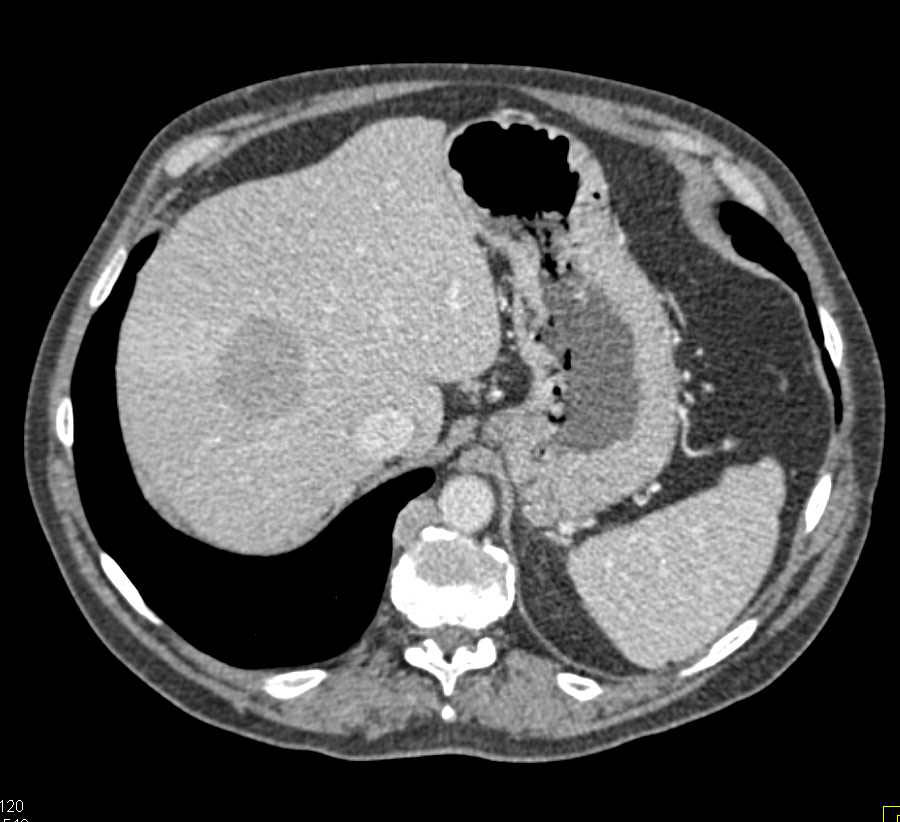

Stomach cancer CT – wikidoc

Gastric Cancer with Extensive Adenopathy – Stomach Case Studies …

Carcinoma of the Gastric Antrum – Stomach Case Studies – CTisus CT Scanning

Gastric Cancer with Extensive Adenopathy – Stomach Case Studies …

Gastric Cancer at the EG Junction – Stomach Case Studies – CTisus CT …

CT scan showing stomach cancer – Stock Image – C021/3358 – Science …

Ulcerating Gastric Cancer – Stomach Case Studies – CTisus CT Scanning

Gastric Cancer with Adenopathy – Stomach Case Studies – CTisus CT Scanning

Recurrent Gastric Cancer – Stomach Case Studies – CTisus CT Scanning

Gastric GIST Tumor – Stomach Case Studies – CTisus CT Scanning

Imaging Findings of Gastric Carcinoma | IntechOpen

Stomach Cancer On Ct Scan

Gastric Carcinoma | Radiology Key